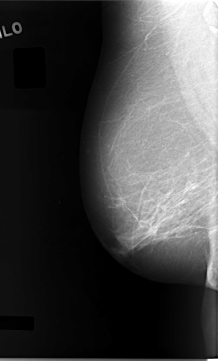

C_0027_1.RIGHT_MLO

RIGHT_MLO LINES 5768 PIXELS_PER_LINE 3504 BITS_PER_PIXEL 12 RESOLUTION 50 NON_OVERLAY